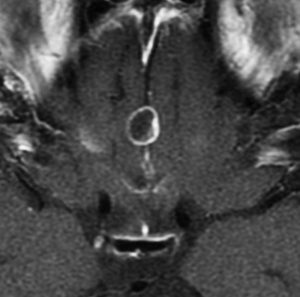

成人の第3脳室内部に局在する頭蓋咽頭腫です。経脳梁法で両側のモンロー孔から全摘出しました。下垂体組織は残っています。これは乳頭状頭蓋咽頭腫と呼ばれるもので,成人にしか発生しません,のう胞がなく石灰化もないのが大きな特徴です。境界が明瞭で柔らかく摘出が簡単なタイプとして知られています。この患者さんも術後に下垂体機能不全も視床下部障害も生じませんでした。